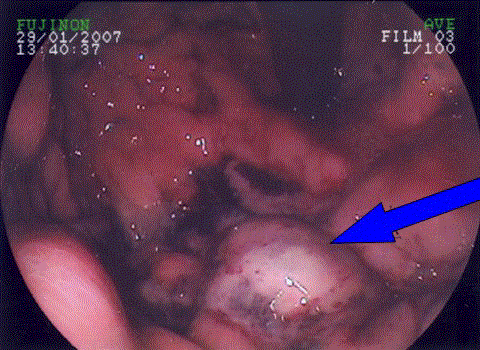

Figure 1. Gastroscopy demonstrating patchy necrosis of the proximal stomach (arrowed) with associated mucosal ulceration.